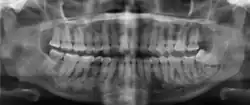

Florid osseous dysplasia of the mandible | |